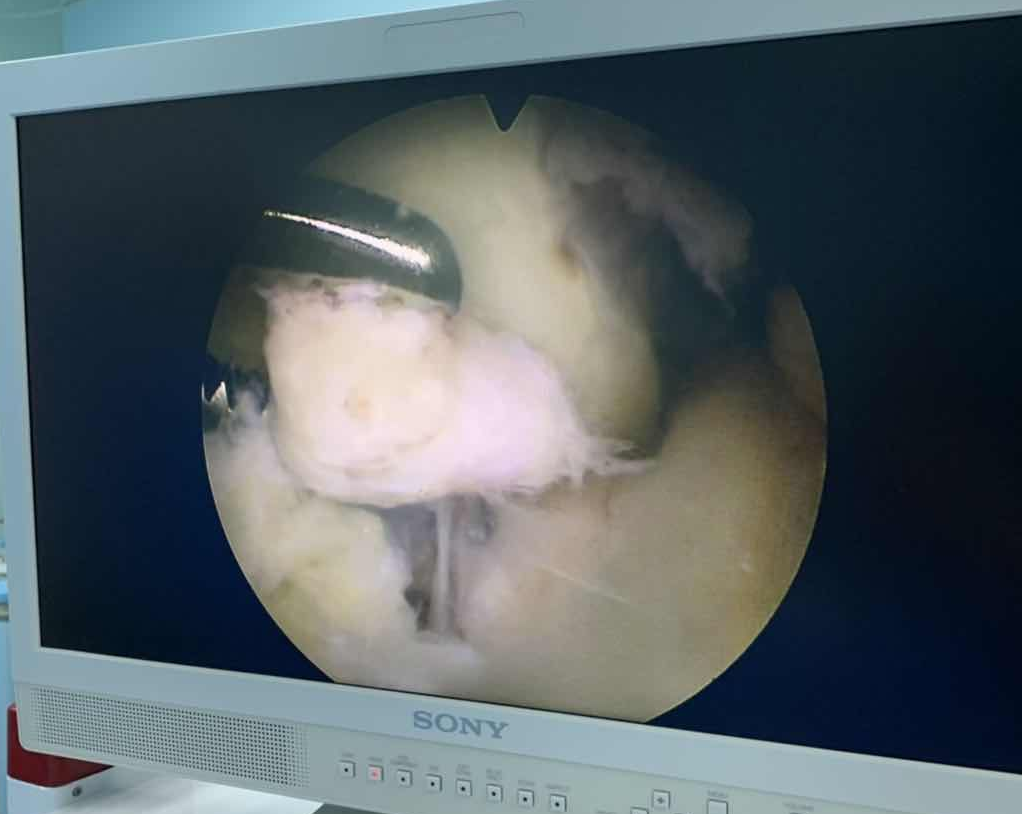

市人民医院骨外科关节镜于2019年9月购置并投入使用,现已经开展了大量关节镜微创手术包括:交叉韧带断裂重建术,半月板修复术,游离体取出及滑膜清理术,髌骨脱位韧带重建术,肩关节镜下肩袖损伤修复术,踝关节镜下踝关节不稳韧带重建术等60余例。因其具有皮肤切口小,创伤小,出血少,痛苦小,康复快等优点,正逐渐为广大患者所接受,关节镜下微创手术,将是未来疾病诊断与治疗的大趋势。

关节镜是一种高新微创技术,原理和胃肠镜差不多,它只有筷子粗细,常用直径只有5毫米,在皮肤上做一个不到1厘米的小切口,就可以把关节镜放入关节内,可以直接观察到滑膜、软骨、半月板及韧带的结构,等于把医生的眼睛放入关节内,有着传统的X光,CT、MRI不可替代的作用,连接微型摄像机,通过光纤照明系统和计算机成像系统,把关节内情况清晰地显示在屏幕上,可以让医生在显示器上清楚地看到关节内放大的影像,进行相应的诊断与治疗。而且通过不同的入路和不同角度的镜头,可以看到关节的每个角落,可以发现其他常规检查发现不了的微小病变。

关节镜可以应用于髋、膝、踝、肩、肘、腕等关节,在骨性关节炎的关节冲洗与清理,半月板损伤的修整与修复,软骨剥脱的修复与移植,增生滑膜的清理,游离体取出,以及交叉韧带断裂重建,肩袖损伤的修复,髌骨脱位韧带重建手术,髋关节撞击,踝关节不稳韧带重建及距骨撞击软骨移植等等手术中起着不可替代的作用,甚至在关节内骨折手术中,辅助关节镜观察关节面复位,能达到常规C型臂透视所达不到的精细程度。